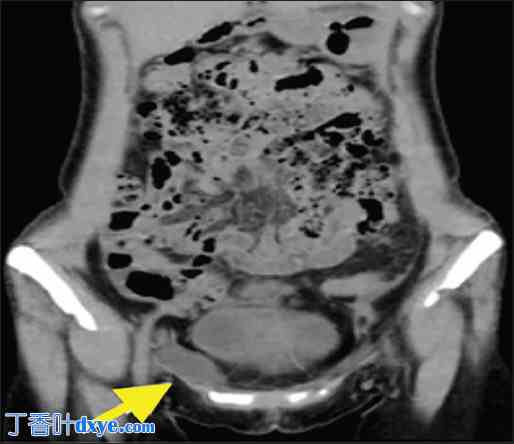

轴位增强腹部CT扫描。右侧腹股沟囊实性肿块(黄色箭头)。

图2

2.jpg

冠状位增强腹部CT扫描。可见一边界清晰的肿块,大小为 4.5 × 2 厘米(黄色箭头所示)。